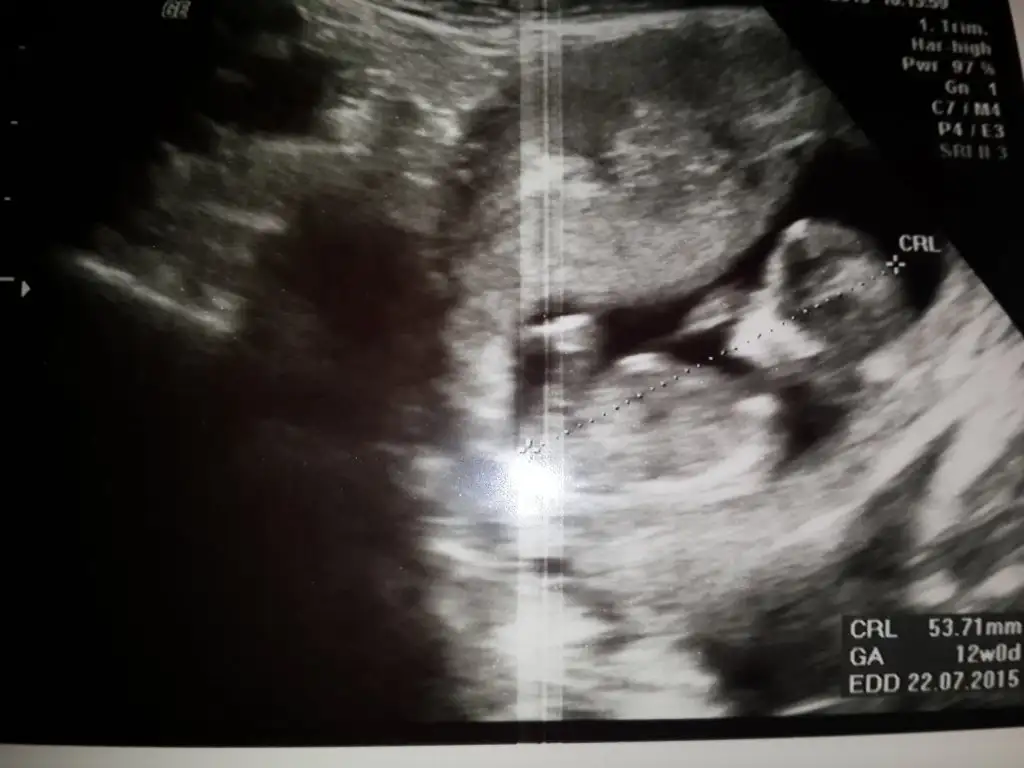

dr soylemeden siz gorun genital nub teorisi ( bebegin cinsiyeti)

IMG_1301.webp IMG_1302.webp IMG_1303.webp IMG_1306.webp

Kiz dedigim foto on haftalikmis zaten canm o haftada hepsi kiz gibi gorunur bilseydim kucuk derdim son fotodan belli erkek bebegin geliyor bence